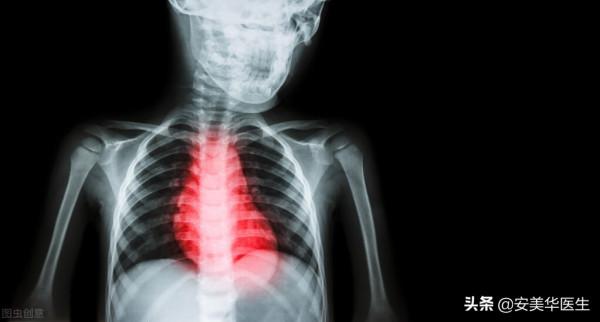

氣短胸悶是什麼病?

氣短、胸悶等不良症狀,首先是冠心病引起的,嚴重者可引起心絞痛。心肌梗死甚至猝死;其次是病毒性心肌炎引起的心肌缺血癥狀,可引起心室肥大和心功能損害。

在現實生活中,一些患者出現呼吸短促、胸悶等不良症狀,對其健康影響很大,不利於提高生活質量。如果不是很嚴重,就要儘快治療。氣短胸悶是什麼病?來看看!